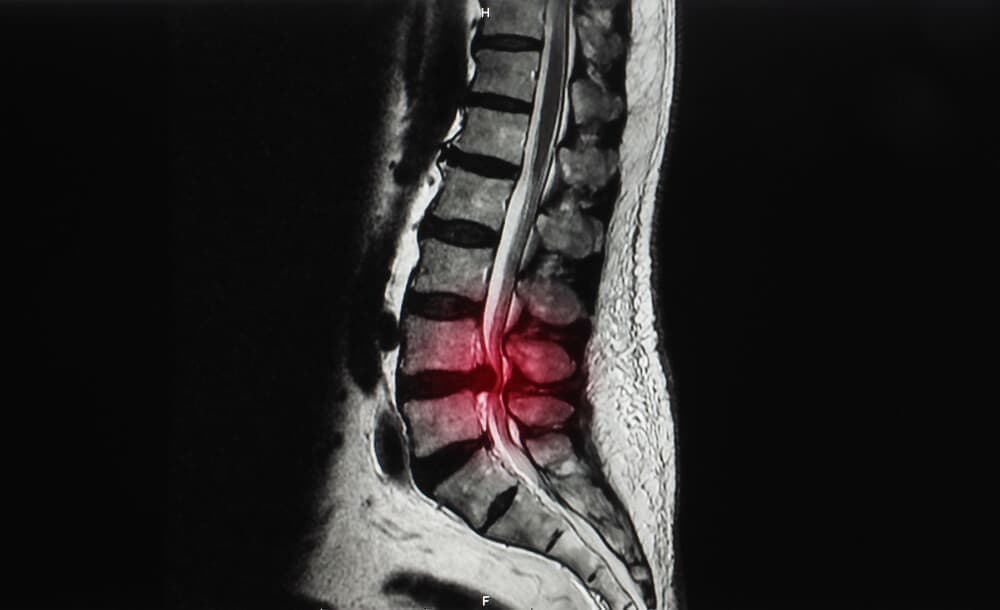

ひどい腰痛で整形外科など病院に行くと、最初にレントゲン検査があるのが一般的です。レントゲン検査は骨の異常を見つけるための検査で、衝撃を受けてずれたり歪んだ腰椎や骨盤が筋肉や靭帯を傷めて激痛のぎっくり腰をもたらしていることは診断できず、シップや痛み止めなどでの対処となるのが一般的です。